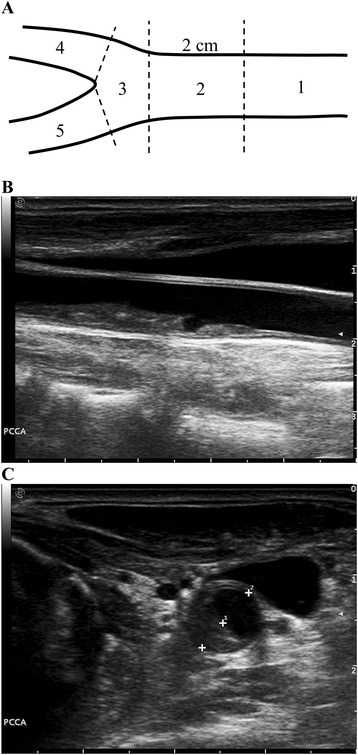

Carotid ultrasound examinations were performed in a 22°C air-conditioned examination room using the Esaote MyLab Twice ultrasound unit in conjunction with a 4–13 MHz linear transducer (Esaote, Genoa, Italy). Subjects lied supine on the examination couch with the neck slightly extended and the head turned away from the side under examination. Using gray-scale ultrasound, the extra-cranial carotid artery was screened longitudinally and transversely. Carotid plaque was identified as a focal thickening >50% of the adjacent intima-media layer [32]. Once a carotid plaque was identified, transverse gray-scale images of the plaque were obtained and the degree of carotid stenosis was expressed as a percentage reduction of the lumen diameter at the most stenotic site. Carotid plaque score was evaluated using an adjusted plaque scoring system [28]. In the scoring system, the carotid artery was divided into five segments: 1. Proximal common carotid artery (≥2 cm proximal to carotid bifurcation); 2. Distal common carotid artery (<2 cm proximal to carotid bifurcation); 3. Carotid bulb and bifurcation; 4. Internal carotid artery; and 5. External carotid artery. The degree of carotid stenosis in each segment was measured and carotid plaque score was expressed as the summation of the degree of carotid stenosis of all segments in both carotid arteries (Figure 1).

Figure 1.

Assessment of carotid plaque score. A). Five segments of the extra-cranial carotid artery: 1. proximal common carotid artery (≥2 cm proximal to carotid bifurcation); 2. distal common carotid artery (<2 cm proximal to carotid bifurcation); 3. carotid bulb and bifurcation; 4. internal carotid artery; and 5. external carotid artery. B). A longitudinal gray-scale image of a carotid plaque in the distal common carotid artery. C). A transverse gray-scale ultrasound image of the carotid plaque in B. The degree of the carotid stenosis is expressed as the percentage reduction of lumen diameter (1-D1/D2 = 41.3%). Carotid plaque score is the summation of the degree of carotid stenosis of the five segments in both carotid arteries.